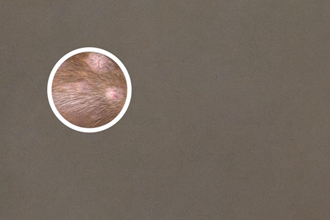

光療是通過使用不同波長的光線照射患者的皮膚,以刺激黑色素細(xì)胞的功能恢復(fù),從而改善白斑癥狀。調(diào)查表明,光療可以增加黑色素細(xì)胞的活性,促進(jìn)黑色素的產(chǎn)生,有助于白斑的恢復(fù)。然而,治療結(jié)果可能因個體差異而有所不同。

常見的光療治療方式包括紫外線照射療法和激光療法。紫外線療法主要通過照射A波、B波或窄譜UVB來治療白斑,而激光療法則使用特定波長的激光光束照射患者的白斑部位。這些治療方法需要在醫(yī)生的指導(dǎo)下進(jìn)行,并且需要一定的療程和間隔。